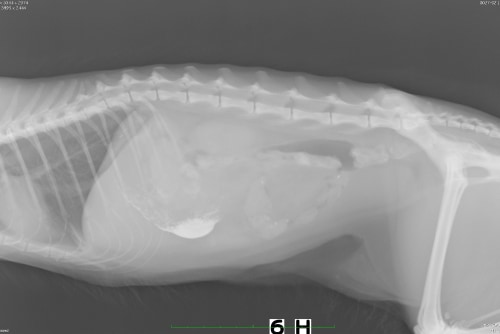

診断・治療

超音波検査から小腸で腫瘍による腸閉塞、また、それに伴い腸に穴が開いている(腸穿孔)が確認されました。物理的な閉塞ため、閉塞部位の切除が必要となるため外科手術による切除を実施しております。術後は下痢が認められるも食欲が改善し、嘔吐もなくなっております。

解説

猫の腸閉塞は、腸内の物質が正常に移動できなくなる状態で、異物の摂取、腫瘍、腸のねじれ(腸捻転、腸重積)などが原因で発生します。主な症状には、嘔吐、食欲不振、腹痛、元気消失、腹部の膨満感が見られ、長期に渡ると腸穿孔(腸に穴があくこと)を引き起こします。特に、嘔吐が続く場合は緊急性が高いです。診断には、身体検査や画像診断(X線や超音波)が用いられます。治療は通常、手術や内視鏡によって閉塞を解除し、必要に応じて腸の修復や異物の除去を行います。早期の発見と治療が予後に大きく影響します。